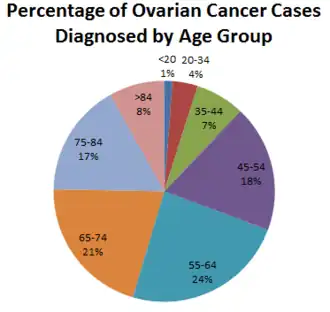

In 2020, new cases occurred in approximately 313,000 women.[21] In 2019 it resulted in 13,445 deaths in the United States.[22] Death from ovarian cancer increased globally between 1990 and 2017 by 84.2%.[23] Ovarian cancer is the second-most common gynecologic cancer in the United States. It causes more deaths than any other cancer of the female reproductive system.[24] Among women it ranks fifth in cancer-related deaths.[25] The typical age of diagnosis is 63.[2] Death from ovarian cancer is more common in North America and Europe than in Africa and Asia.[5] In the United States, it is more common in White and Hispanic women than Black or American Indian women.[22]

Increased age (up to the 70s) is a risk factor for epithelial ovarian cancer because more mutations in cells can accumulate and eventually cause cancer. Those over 80 are at slightly lower risk.[29]